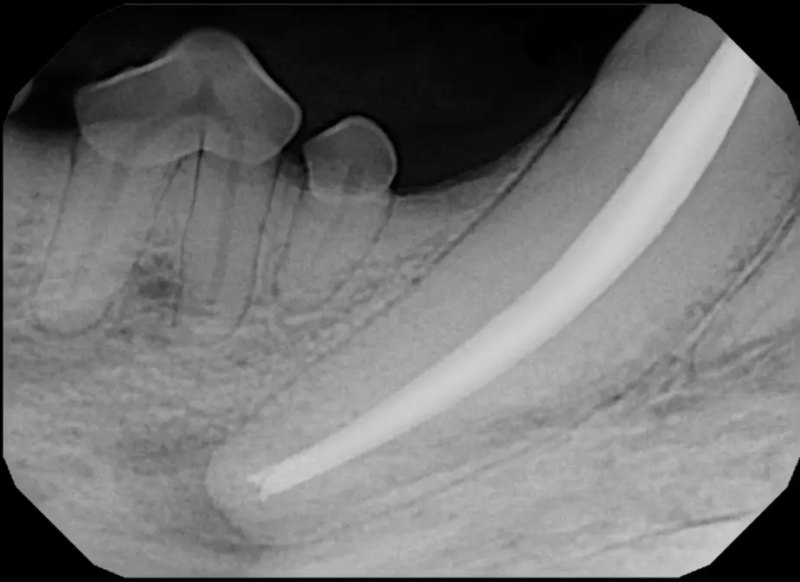

Root Canal Therapy

Root canal therapy is an excellent option for saving important teeth that have been fractured or are determined to be non-vital. The procedure is performed exactly as it would be for a human, except your pet will be dreaming peacefully under anesthesia. In many cases, root canal therapy is much easier on your pet than extraction, and preserves the structure of the tooth. It is important to have the root canal x-rayed periodically to monitor for any problems.